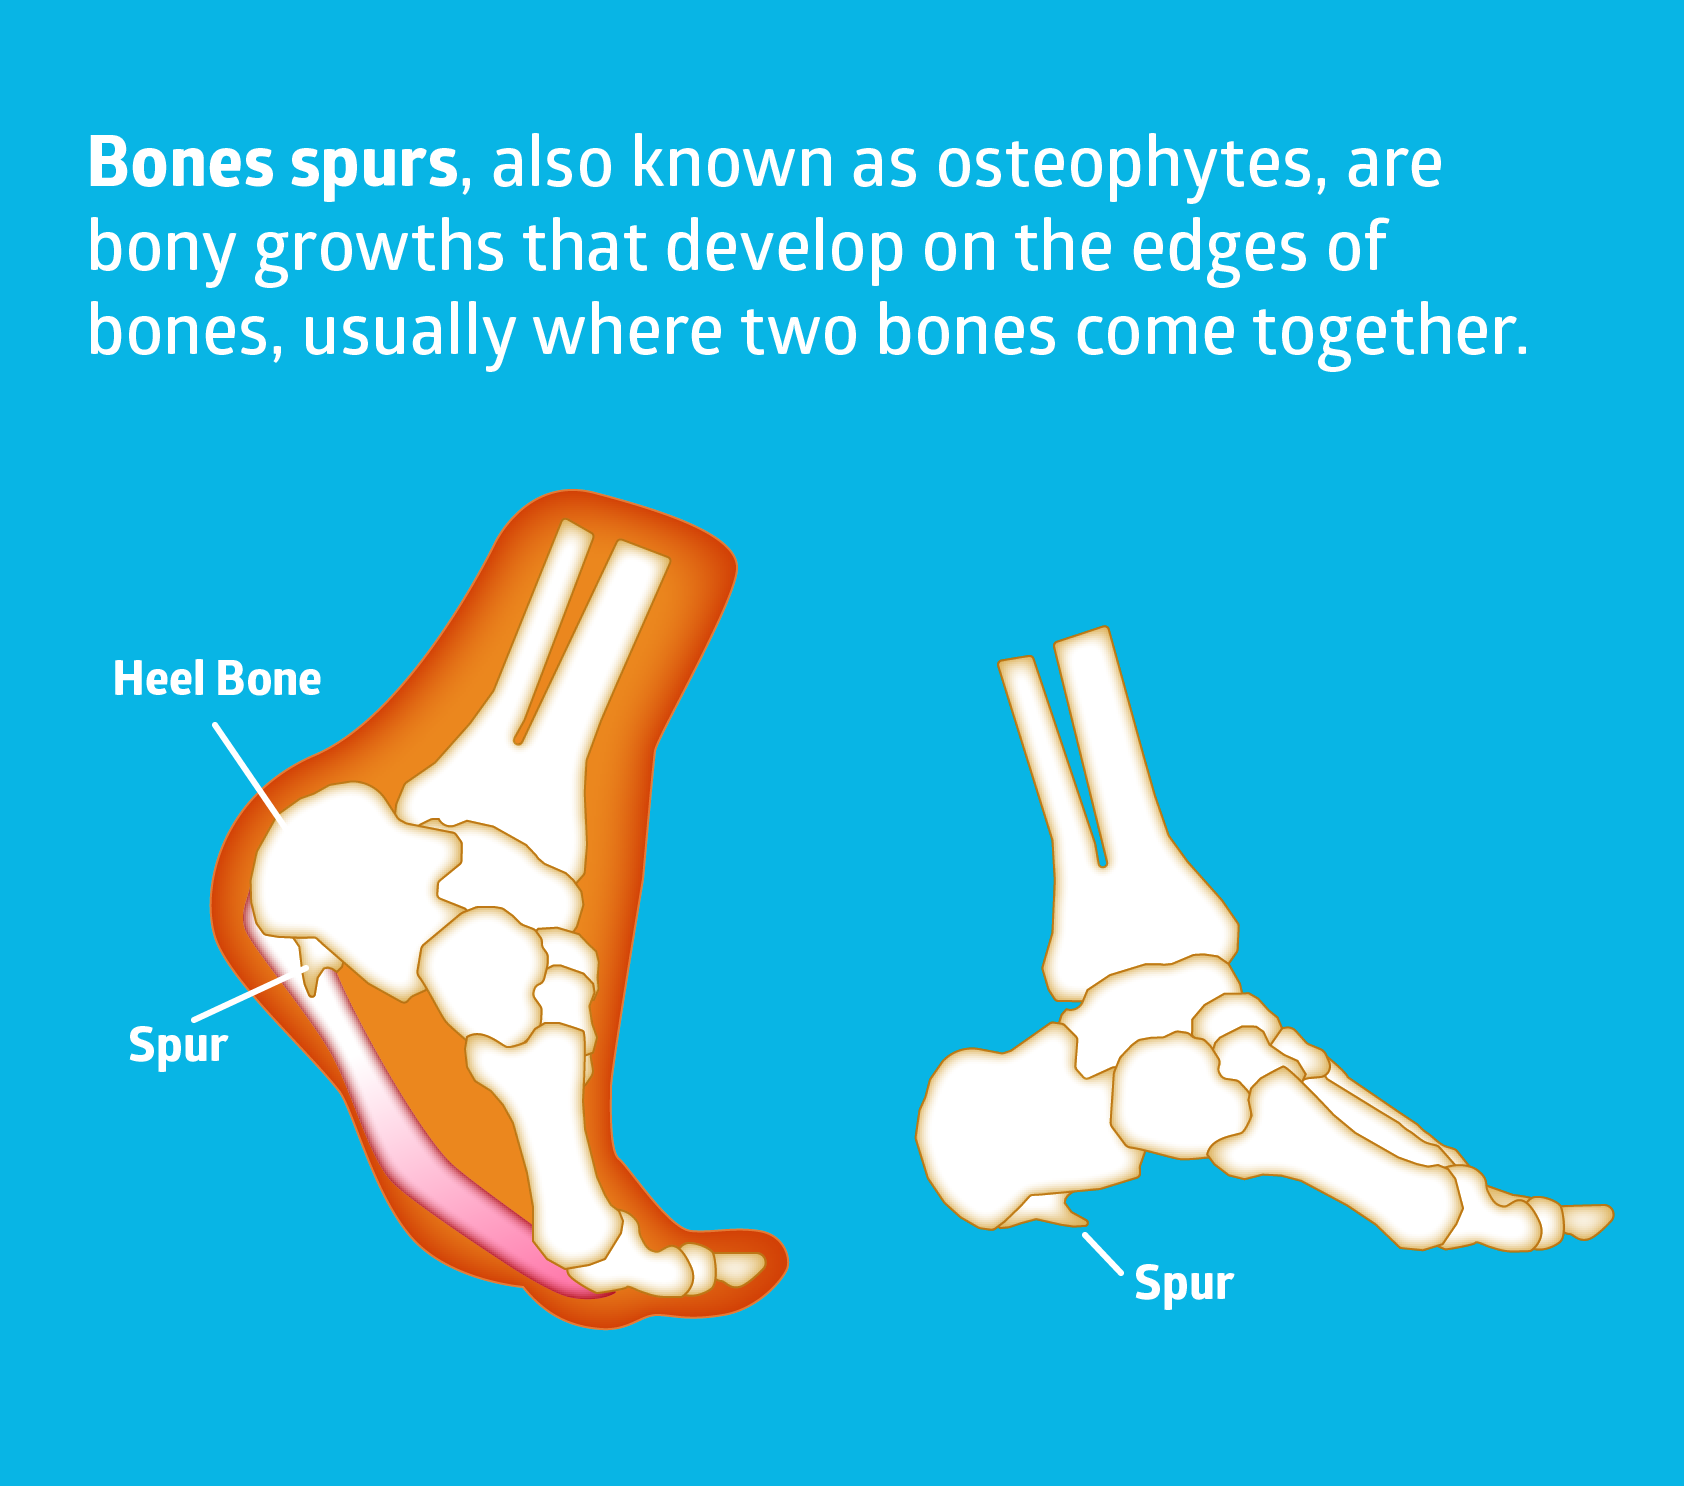

Bone Spur – Osteophytes, Causes, Signs, Symptoms & Treatment

What Are Lumbar Osteophytes (Bone Spurs)? | Bone spurs, Spurs, Spine …

Bone Spurs | The Advanced Spine Center

Bone Spurs: Diagnosis, Causes, Symptoms, and Treatment

Do Bone Spurs Grow?

Bone spurs in neck (cervical osteophytes): Causes, symptoms, diagnosis …

Are Bone Spurs Genetic?